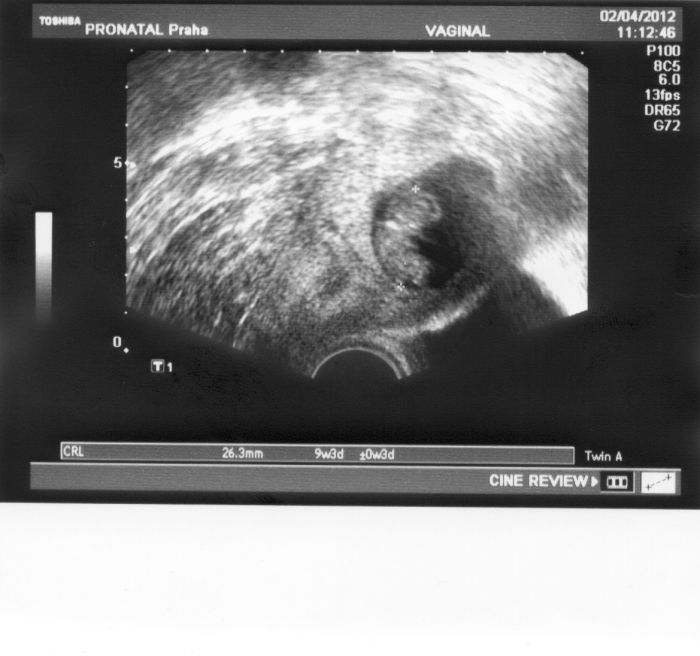

Ahojky. Sáro, to je super. Tak zítra budeš také těhulka. Hlavně žádný stres a užívej si to, ať máš za pár týdnů tak krásný obrázek, jako jsem dneska z UZ dostala já. Na Tvém ale určitě budou 2 miminka

Dneska bylo miminko na UZ tak krásně vidět,že se mi až chtělo brečet. Viděla jsem ručičky i nožičky a srdíčko

Přikládám fotečku našeho andělička

Ahoj Leni krásnááááá fotečka